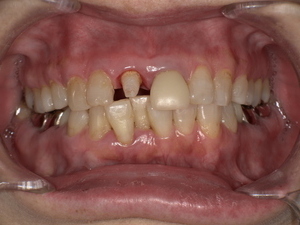

Before(治療前)

転倒の衝撃により、上の前歯の被せ物(クラウン)が外れ、歯の大部分が欠けている状態でした。

このままでは見た目の問題だけでなく、噛む力によって歯がさらに割れる可能性もあり、早期の治療が必要な状態でした。